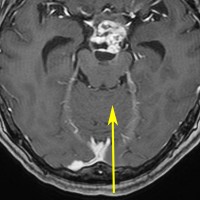

小さな松果体奇形腫です。

OTAでこの奇形腫を見ようとする場合に,テントを静脈洞交会の低い位置まで切断しなければ,直静脈洞の横から松果体部をみることはできません。また,黄色の矢印の方向に視野が入るので,まず最初に邪魔になるのは小脳上極です。上小脳層を左右ともに十分剥離すると,小脳が可動化して,その向こうに,precentral cerebellar veinが見えます。このveinをガレン大静脈への流入部から小脳前面に沿って剥離していくと,小脳上極がさらに可動化して松果体への視野が開ます。

松果体腫瘍の手術では,中脳背面を見る必要があります。特に上丘とそれに連続する後交連 posterior commissureを十分に観察するために周囲組織の剥離を行います。具体的には迂回槽と下丘の周囲のクモ膜組織を剥離します。対側中脳と迂回槽を見る時に妨げになるのが,緑の矢印で示した直静脈洞です。テントが長く切断してあって直静脈洞が大脳鎌と一緒に動かせると対側を見るのがとても簡単になります。